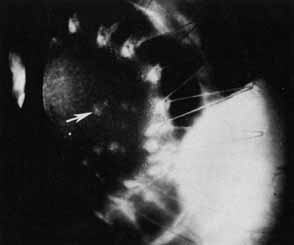

Retinal status must be evaluated but may be limited by the view to the posterior pole through a diseased cornea. Contralateral retinal examination may yield information regarding glaucoma, macular degeneration, and overall retinal status. If the view is unsatisfactory, B-scan ultrasonography is indicated.